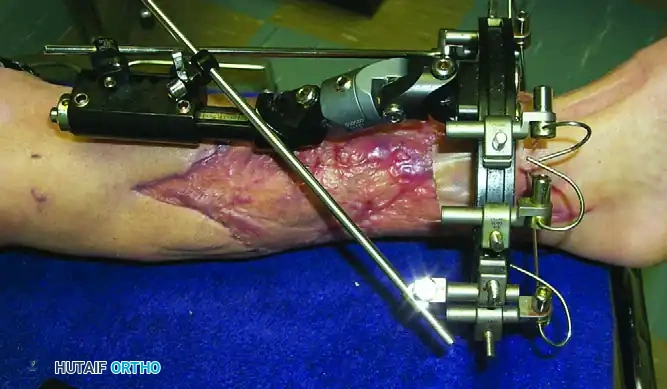

- Incision: Make a longitudinal stab incision (1-2 cm) through the skin. Do not use a puncture technique, as skin tension around the pin leads to necrosis and infection.

- Blunt Dissection: Use a hemostat to bluntly dissect down to the periosteum. Insert a tissue protection sleeve (drill guide) firmly against the bone.

- Pre-drilling: Always pre-drill the near and far cortices using a sharp drill bit. Use continuous saline irrigation to cool the drill bit. Thermal necrosis from drilling is the primary cause of premature pin loosening and ring sequestrum formation.

- Pin Placement: Insert the half-pin manually or on low speed. Ensure the pin engages the far cortex but does not protrude more than 1-2 threads to avoid tethering far-side soft tissues.

Increases in intracompartmental pressures can occur if pins traverse a tense muscle compartment, leading to bleeding or edema within the fascial envelope.

* Management: High index of suspicion in high-energy trauma. If compartment syndrome is diagnosed, immediate four-compartment fasciotomy is required.